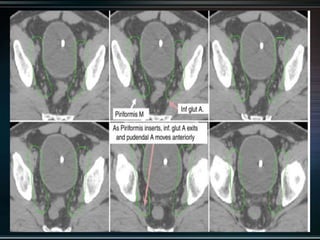

RTOG GU Consensus on pelvic LN CTV volumes:

 Commence contouring the pelvic CTV LN volumes at the L5/ S1

interspace (the level of the distal common iliac and proximal

presacral lymph nodes).

 Place a 7-mm margin around the iliac vessels connecting the

external and internal iliac contours on each slice, carving out

bowel, bladder, and bone.

 Contour presacral lymph nodes from S1 through S3, posterior

border being the anterior sacrum, and anterior border

approximately 10 mm anterior to the anterior sacral bone

carving out bowel, bladder, and bone.

 Stop external iliac CTV lymph node contours at the top of the

femoral heads (bony landmark for the inguinal ligament).

 Stop contours of the obturator CTV lymph nodes at the top of

the symphysis pubis.